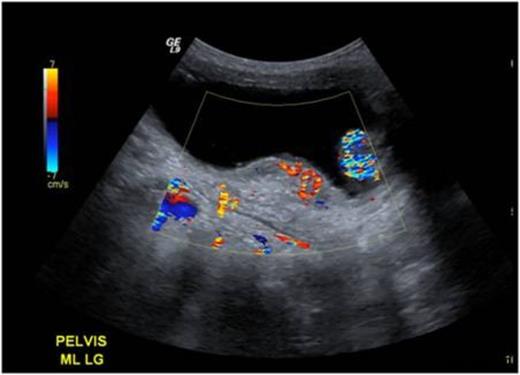

A previously well 2-year old boy presented with acute retention of urine requiring catheterisation. Renal tract ultrasonography revealed a large right-sided bladder diverticulum and a 2.2 x 1.3 x 3.6 cm lobulated thickening on the posterior bladder wall, which was associated with increased vascularity on Doppler imaging (Figure 1).

Ultrasound images demonstrating a posterior bladder wall lesion with increased vascularity